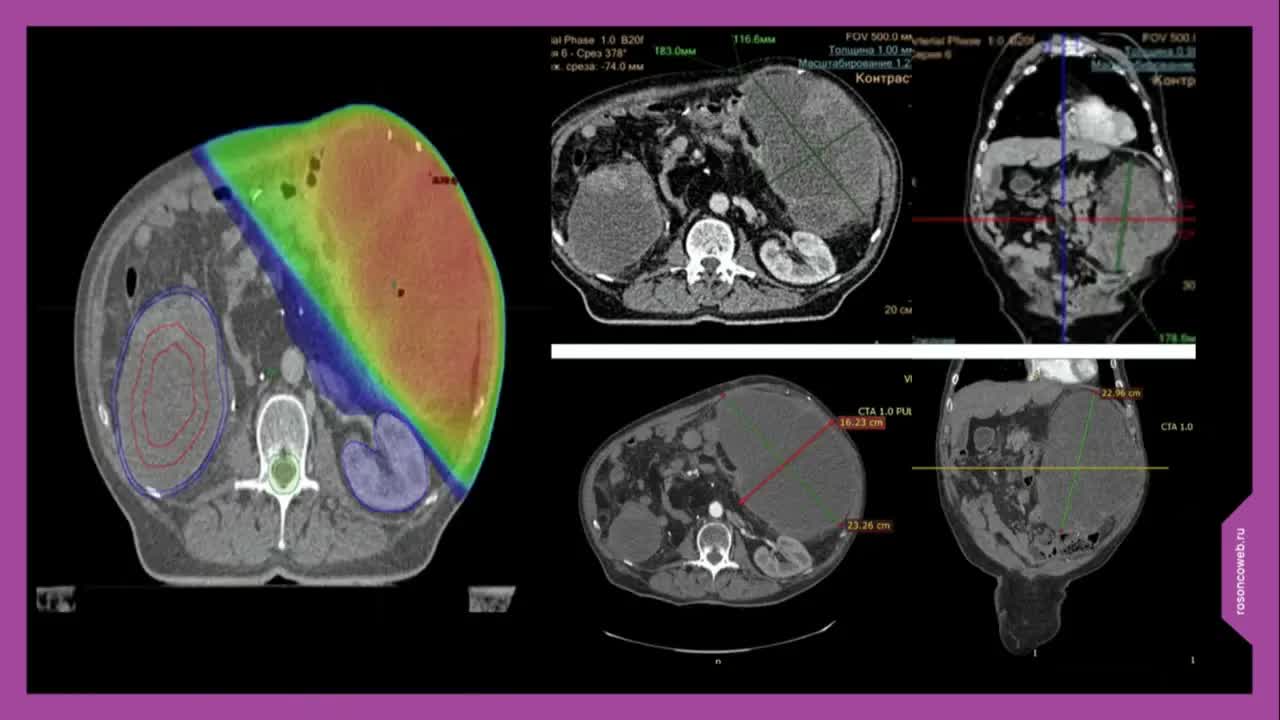

Комбинированное лечение первично-нерезектабельного рецидива забрюшинной липосаркомы